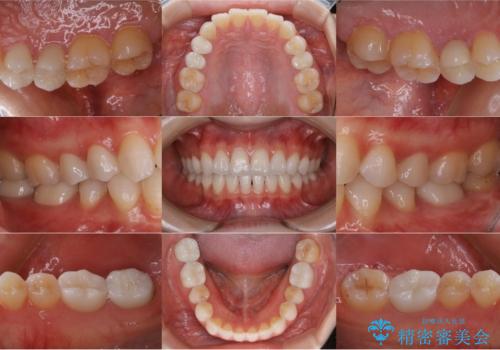

- 引っ越しを期に、悪いところを全部治してほしいとご来院頂きました。

白い被せ物で一見綺麗に見えますが、適合が悪い詰め物や、セラミックが欠けているところが複数認められました。虫歯になってしまっているところもあり、全体的に治療しました。

右下の一番奥の歯は、元々かなり深いところまで削られていたため、歯周外科処置を行った上で補綴処置を行いました。

元々噛む力が強く、日常的に歯ぎしりもされるとの事で、セラミックが欠けてしまっていました。歯が割れてしまうリスクを軽減させるため、歯全体を覆うクラウンをメインに補綴治療を行いました。